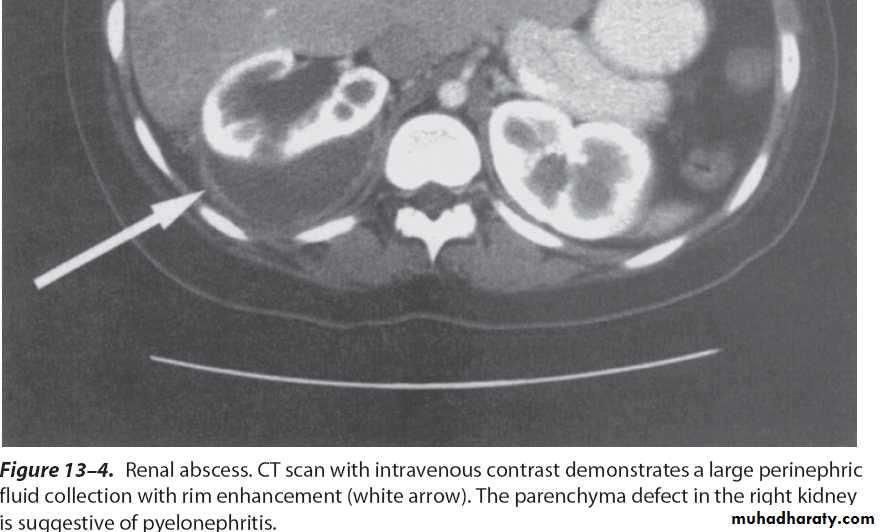

Crescent sign of perinephric abscess complicated from a pyelonephritis

Percutaneous drainage by wide bore for the thick pusWhat's management?